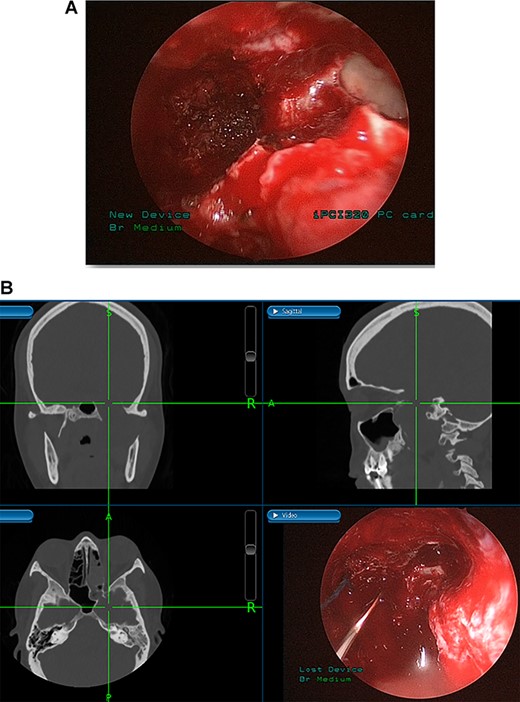

(A) Image-guided tumor removal from petrous carotid artery. (B) Image-guided intraoperative picture status post-complete tumor removal from trigeminal and middle cranial fossa.

(A) Endoscopic view of the final surgical cavity after tumor removal. (B) Image-guided tumor removal from cavernous carotid artery.

The patient underwent an image-guided endonasal endoscopic tumor removal starting by endoscopic medial and posterior walls maxillectomies to control the tumor removal from the lateral sphenoid sinus and the infratemporal fossa after cauterization of the maxillary artery and sphenopalatine artery branches feeding the tumor. The tumor was dissected and removed from the cavernous (Fig. 3A) and petrous carotid artery in the middle cranial fossa (Fig. 3B). The middle cranial fossa’s dura was intact during the tumor removal (Fig. 3C). All the steps of tumor removal were controlled and monitored under image-guided navigation for accurate localization of tumor removal and avoidance of violation to the middle cranial fossa’s dura, or the brain, and the internal carotid artery in its cavernous and petrous segments (Fig. 4a and b).

Tumors in the infratemporal fossa require extensive approach such as middle fossa extraduaral approach, infratemporal fossa extradural approach, transmaxillary approach, transmandibular approach or transcervical approach. Complications from these procedures include cosmetic problems, facial nerve dysfunction, hearing loss and dental malocclusion. Image-guided endoscopic surgery allows for the preservation of intracranial structures, internal carotid artery and cranial nerves. Moreover, this procedure aids in rapid localization of the anatomical structures and meticulous intervention restricted to tumor margins. The screen is divided into four sections allowing visualization of the tumor from axial, coronal and sagittal views [10].